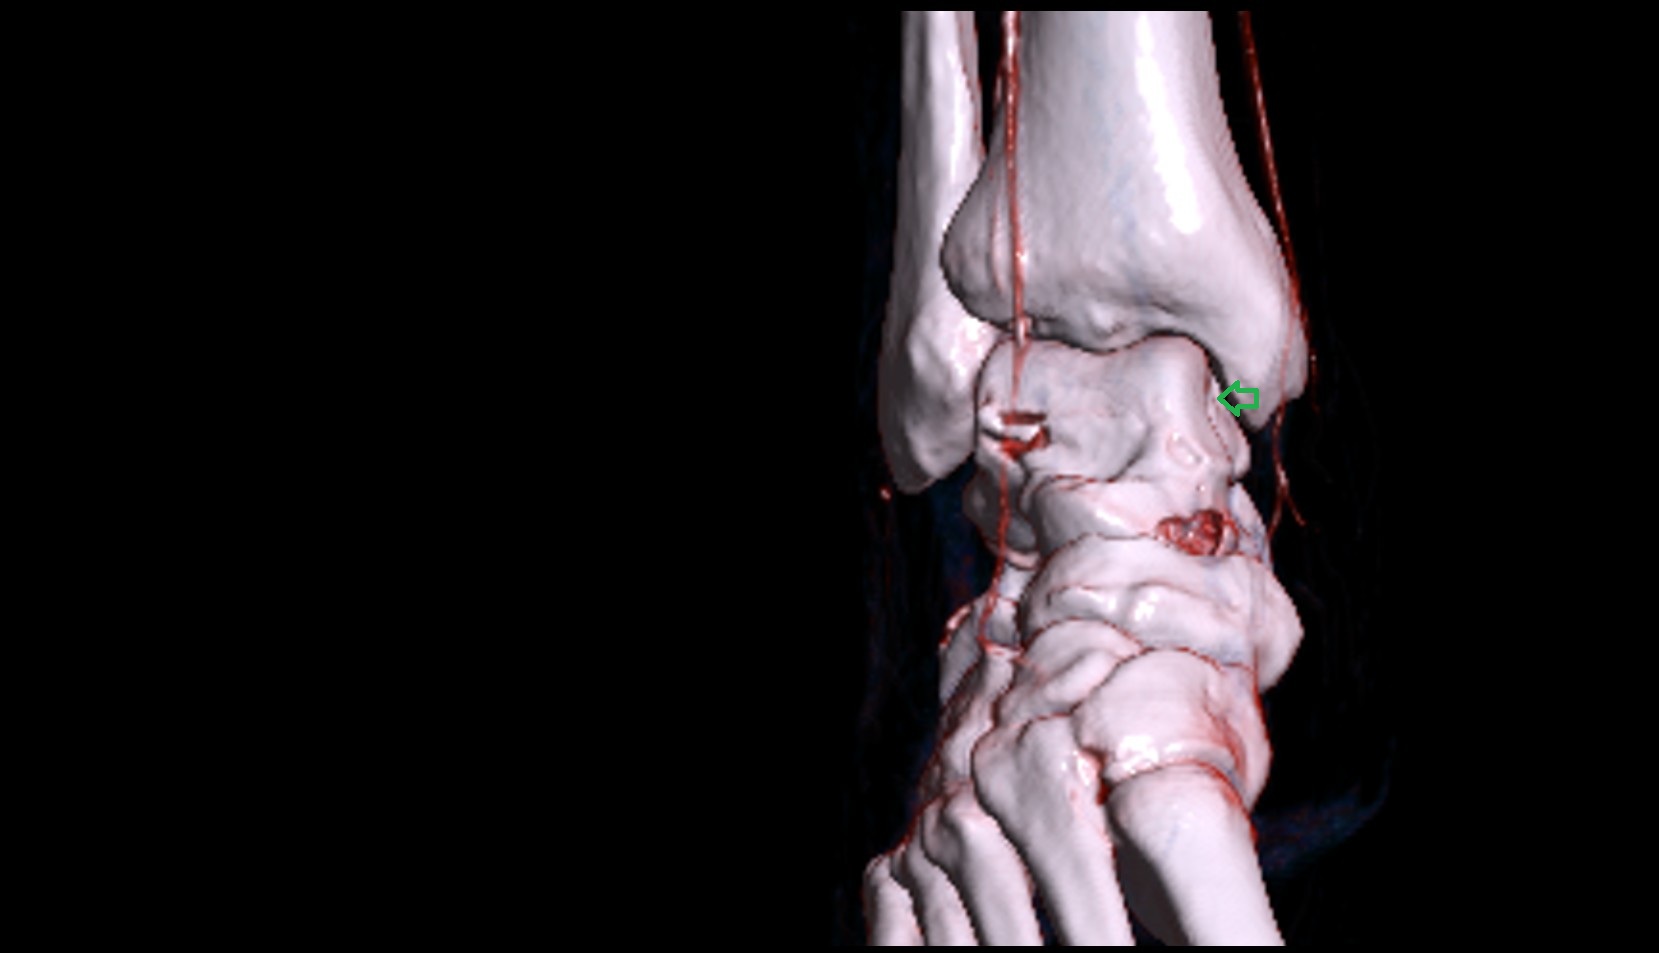

- Talus

- Calcaneus

- Medial malleolus

- Lateral malleolus

- Ankle joint

- Talocalcaneal joint